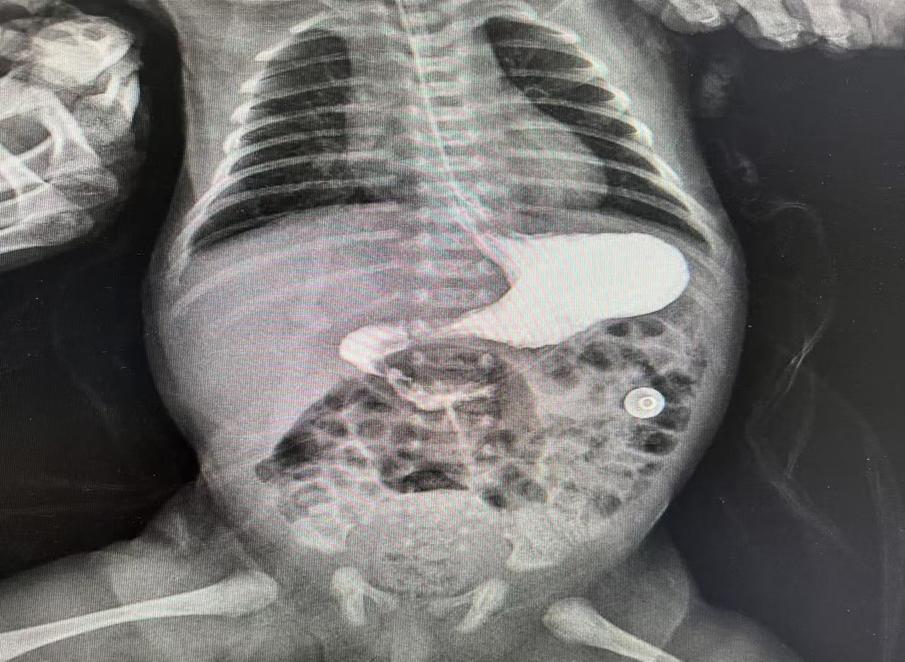

術(shù)后復(fù)查十二指腸已通暢